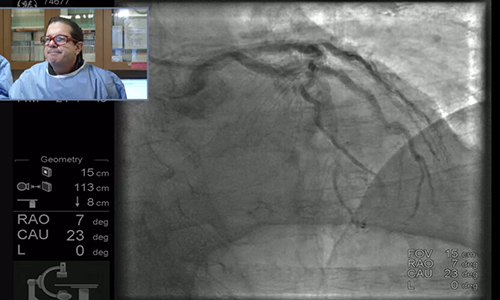

Complex PCI Case with Dr. Paul Teirstein

Dr. Teirstein expertly approaches a previously failed PCI in a lesion with heavy calcification requiring the use of rotational atherectomy, advanced access techniques, and physiological significance measurement.